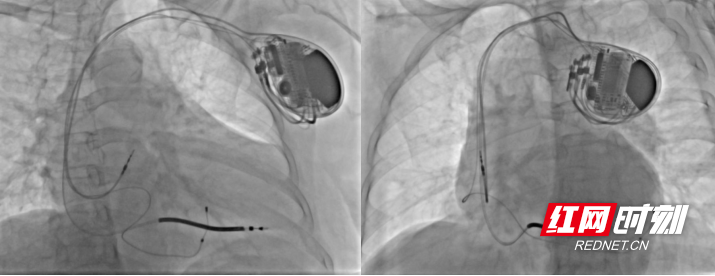

为了给患者制定合适治疗方案,龙双祁团队多次组织多学科会诊,结合患者病情、身体状况及最新诊疗指南,最终确定采用CRT-D(心脏再同步化治疗除颤器)植入术。“CRT-D是目前先进的心脏器械治疗手段,既能解决心脏收缩不同步的问题,又能应对恶性心律失常,相当于给心脏上了‘双保险’。”

手术当天,心血管内科在麻醉科等相关科室的密切配合下,手术团队凭借精湛的技术,顺利为患者完成CRT-D植入术。术后第一天,患者就明显感觉到胸闷、气促的症状有所缓解;随着术后恢复,她的活动能力明显提升,从起初的卧床难起,逐渐能自主下床散步。

在后续定期随访复查中,患者恢复情况持续向好。心脏形态逐步回缩,心功能指标稳步提升。近日,心脏超声复查结果更带来好消息,她的EF值已恢复至54%,成功达到正常范围。这标志着患者实现了心脏结构与功能的“逆重构”,达成生物学康复。此前折磨她半年之久的胸闷、气促、头晕黑矇等症状,也已彻底消失。